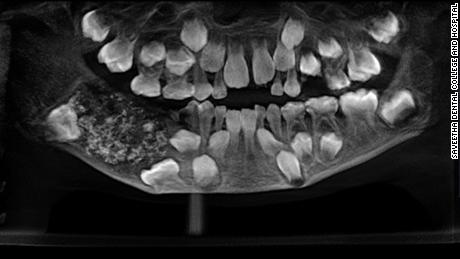

Doktorët gjejnë 526 dhëmbë në gojën e një 7 vjeçari në Indi

Një djalosh 7 vjeçar i cili po ankonte nga dhimbja e nofullës, i janë gjetur 526 dhëmbë brenda gojës së tij, thotë spitali në Indi ku edhe ishte trajtuar.

Kur doktorët skanuan gojën e tij, ata gjeten një qeskë në pjesën e poshtme të mbushur me “dhëmbë anormal” tha Prathiba Ramani, drejtuesja e Patologjisë Orale dhe Maksilofaciale në Kolegjin dhe Spitalin Stomatologjik Saveetha.

Pasi që gjetën qeskën, dy doktorët e hoqën atë nga goja e 7 vjeçarit. Grupit të Ramanit iu deshën 4 deri në 5 orë të zbrazin qeskën, të konfirmojnë dhe zbulojnë qindra dhëmbë, transmeton CNN.

“Aty ishin 526 dhëmbë nga 0.1 milimetër deri në 15 milimetra. Edhe dhëmbi më i vogël kishte kurorë dhe rrënjë”, tha ajo.